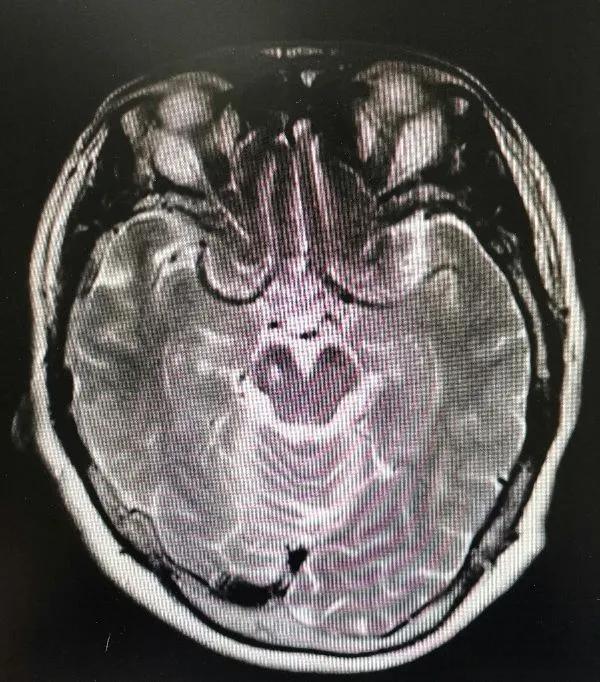

脑梗死软化灶是脑梗死患者在CT检查中常见的一种影像学表现。它指的是脑梗死后,由于脑细胞凋亡、坏死而遗留下的空腔,通常由脑脊液填充。这种软化灶的出现,意味着患者的脑梗死已经进入陈旧期,且可能经历了多次脑梗死事件。